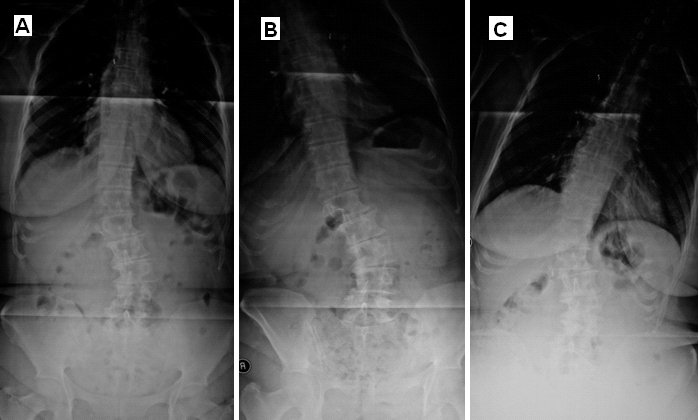

Dejeneratif Lomber Skolyoz Direkt Grafisi

Resim 1: Lomber skolyozun derecesi (20°), L3-L4 seviyesinde skolyoz nedeniyle oluşan yana kayma (listezis) ve dejeneratif değişiklikler görülmektedir.